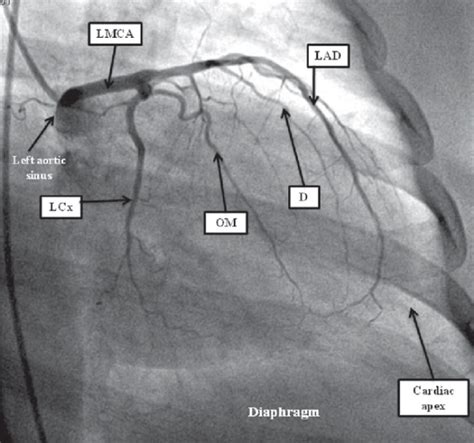

Left coronary artery wikidoc Cath lab nursing, Cardiac